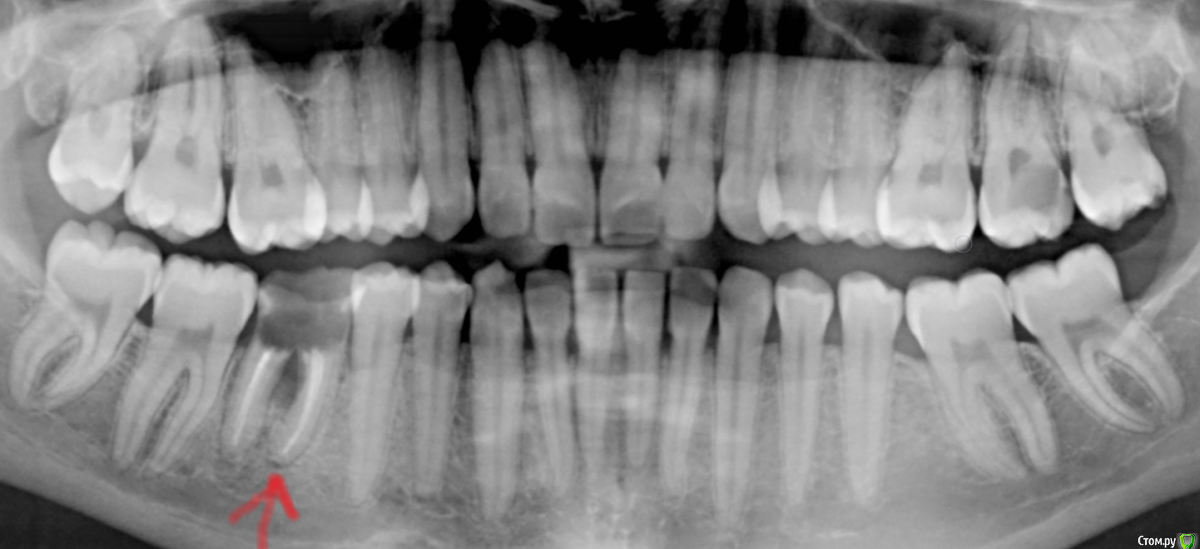

Добрый день! Подскажите, нужно ли ставить брекеты? И можно ли это сделать, если у меня стоит имплантат (на снимке где оранжевая стрелка). Можно ли удалить имплантат и поставить брекеты? Боюсь, что прикус неправильный и в будущем могут сточиться зубы или еще что-нибудь. И если да, то на имплантат можно ли поставить брекеты? В детстве нижняя шестерка, которая с противоположной стороны от имплантата, ее удалили и зуб мудрости туда сместился и между зубами есть расстояния конечно, но некритично. А там где имплантат было большое расстояние и его надо было закрыть, поэтому поставила имплантат. Как вообще быть? Мне 27 лет.